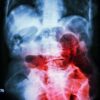

Endoscopic Appearance of a Rectal Ulcer

An endoscopic image would show a shallow or deep erosion in the rectal lining. The ulcer’s edges might appear irregular, with a reddish-brown or yellowish base. The surrounding rectal mucosa might appear inflamed or swollen. The endoscopic image would clearly differentiate the ulcer from the healthy mucosa. The depth of the ulcer and the presence of any exudates (pus or fluid) should be noted in the image description.